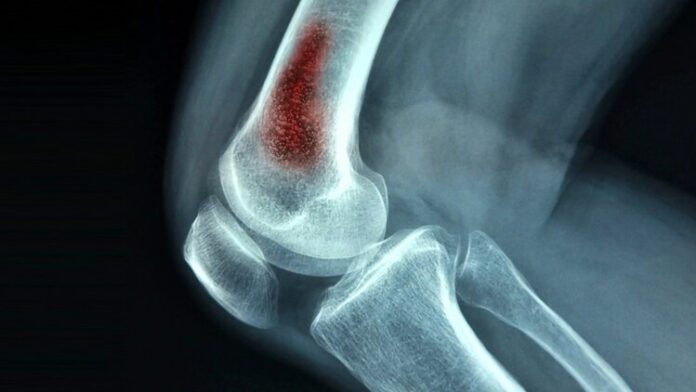

How Scientists Tackle Chronic Osteomyelitis using Bioactive Glass

If you asked doctors how to treat chronic osteomyelitis, they would likely all say the same thing: antibiotics, amputation, or bone grafts. However, if...